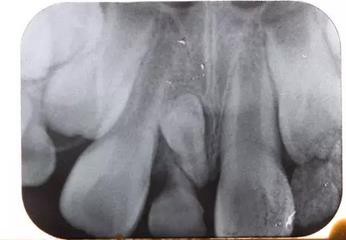

患兒,男,8歲半,混合牙列,11、12均已萌出,其間有一重度磨耗的51滯留,家長(zhǎng)一直不知怎么回事,因?yàn)槊烙^問(wèn)題,至當(dāng)?shù)卦\所給予檢查,也許條件受限沒(méi)有X光牙片機(jī)的緣故,建議直接拔除51,然后矯正關(guān)閉間隙,家長(zhǎng)不放心,來(lái)診,常規(guī)拍攝X線片發(fā)現(xiàn)乳牙滯留和間隙存在的原因是有一埋伏倒置多生牙的緣故,遂建議拔除滯留的51和埋伏的多生牙,然后擇期矯正。

X線片:51牙根基本吸收,下方顯示倒置多生牙。